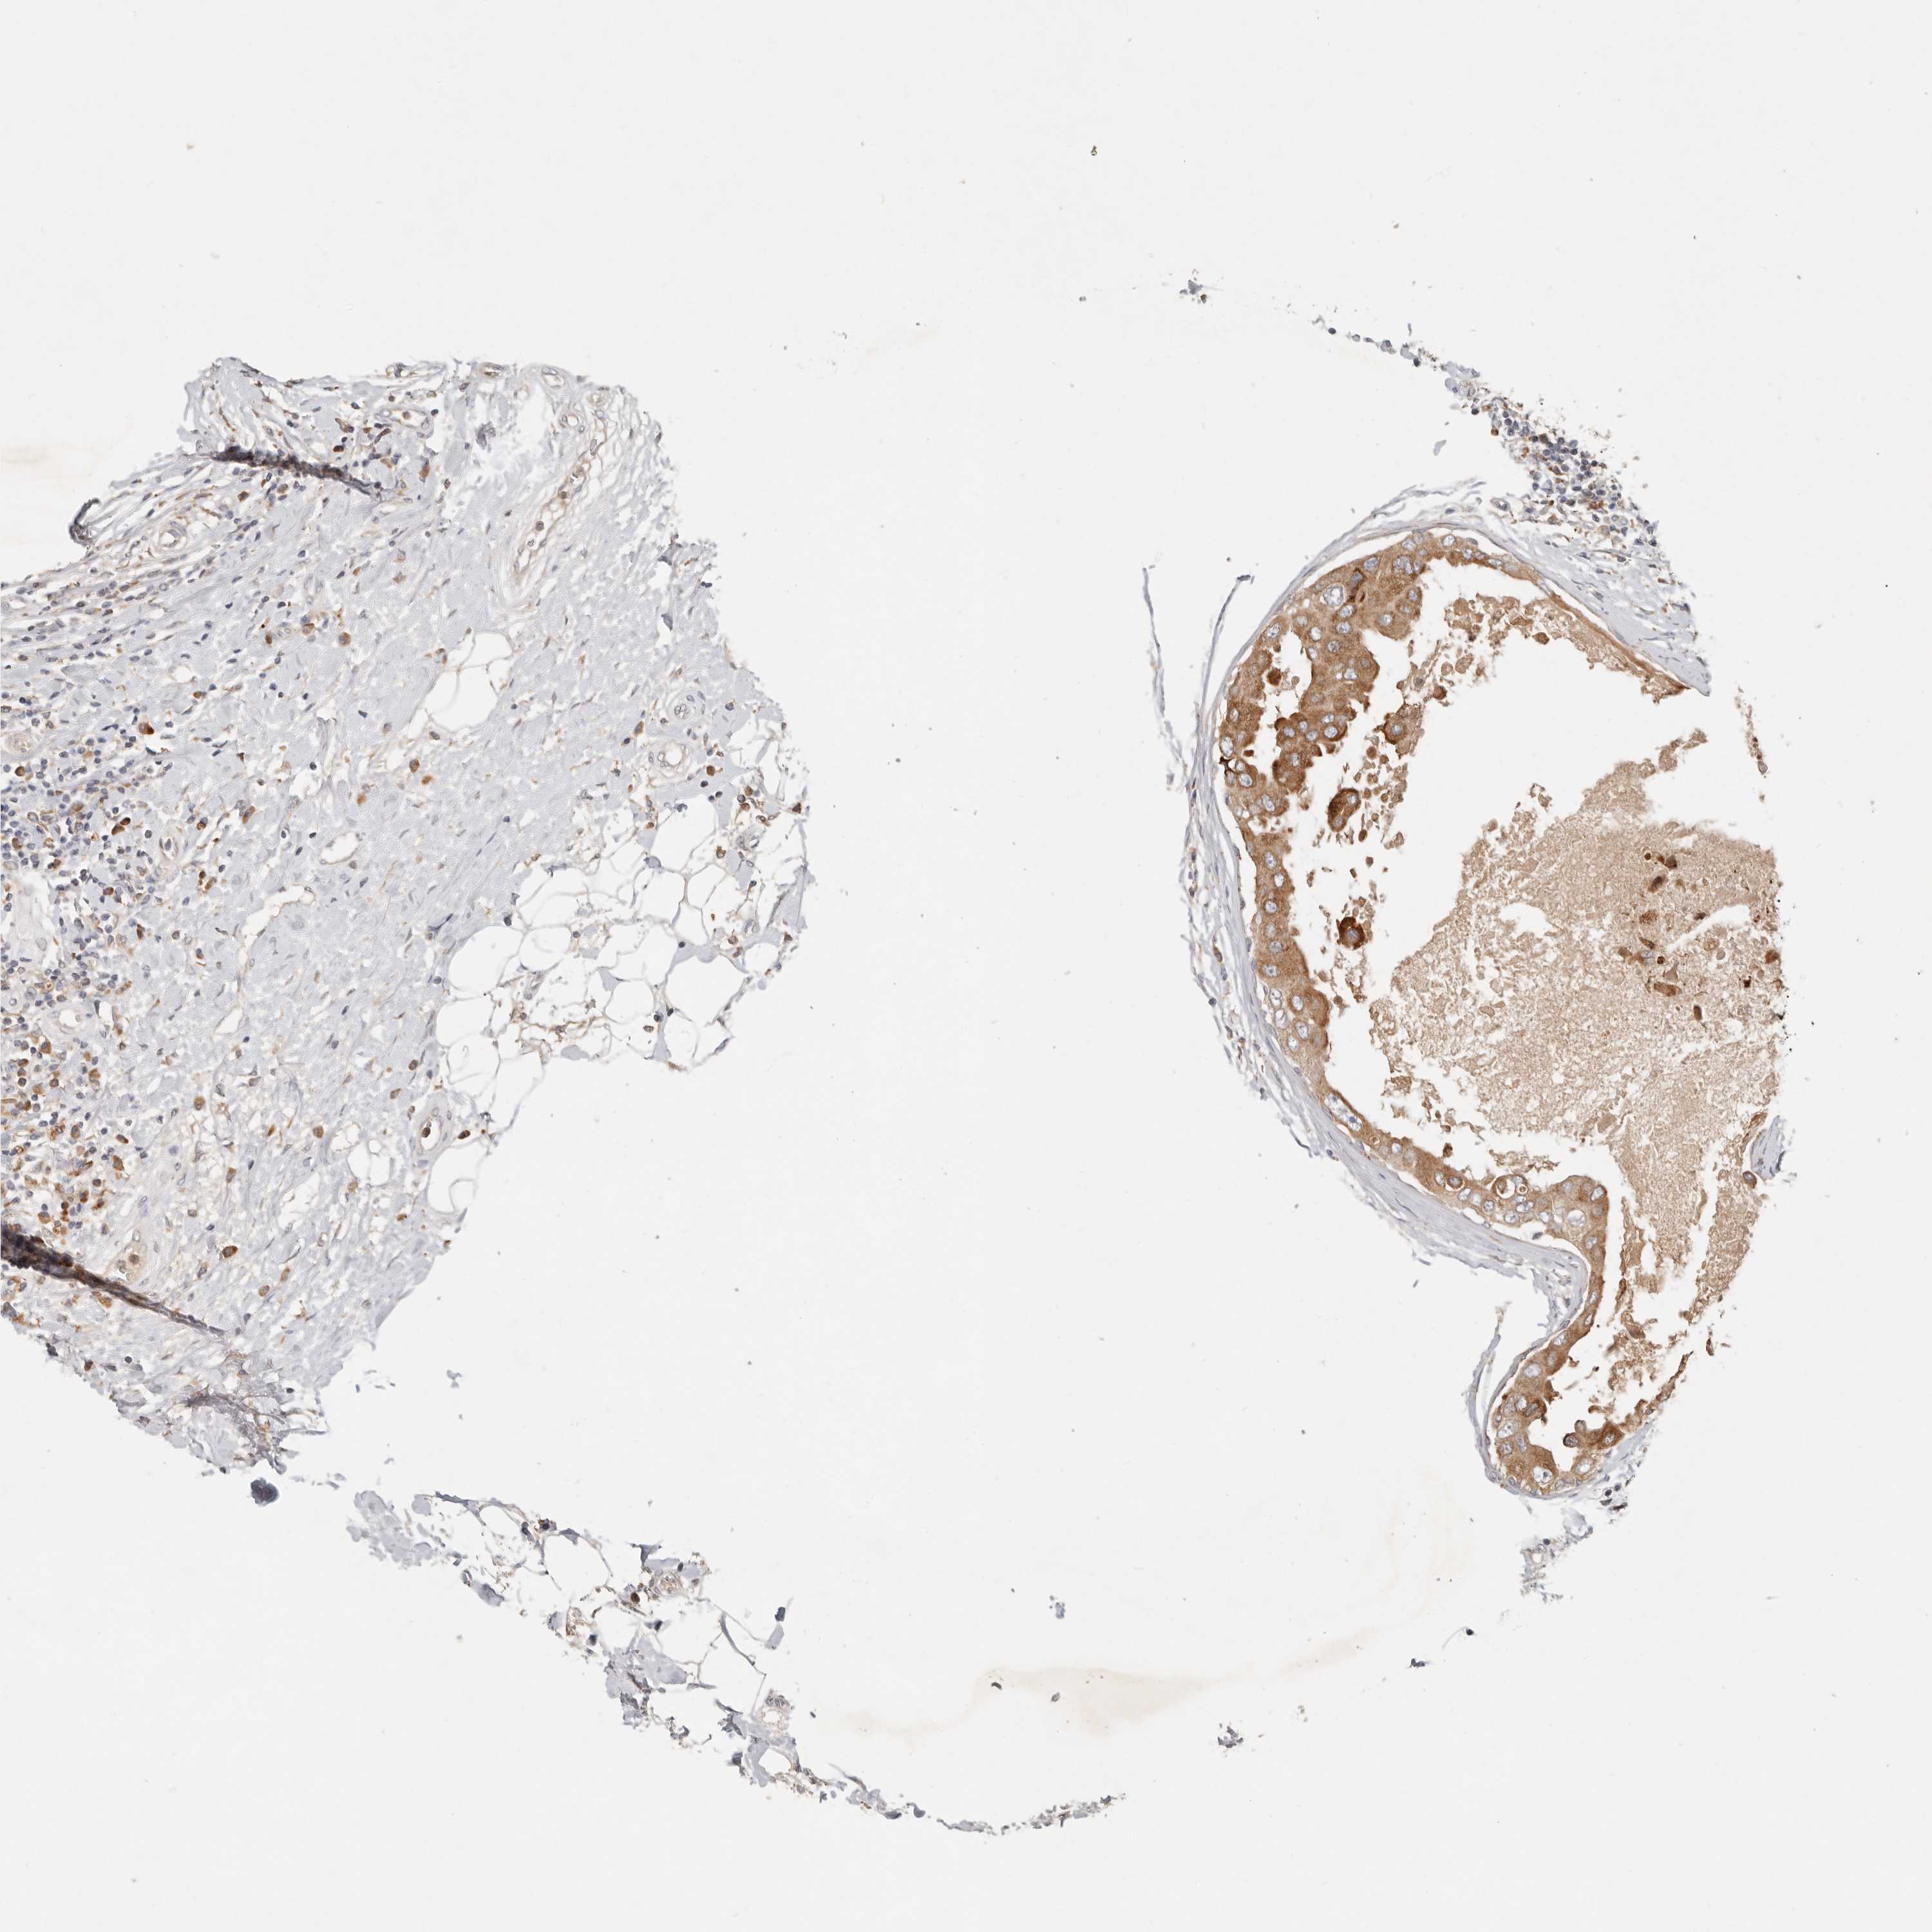

CANCER BREAST CANCER Show tissue menu

BRCA TCGA BRCA VALIDATION PROTEIN EXPRESSION